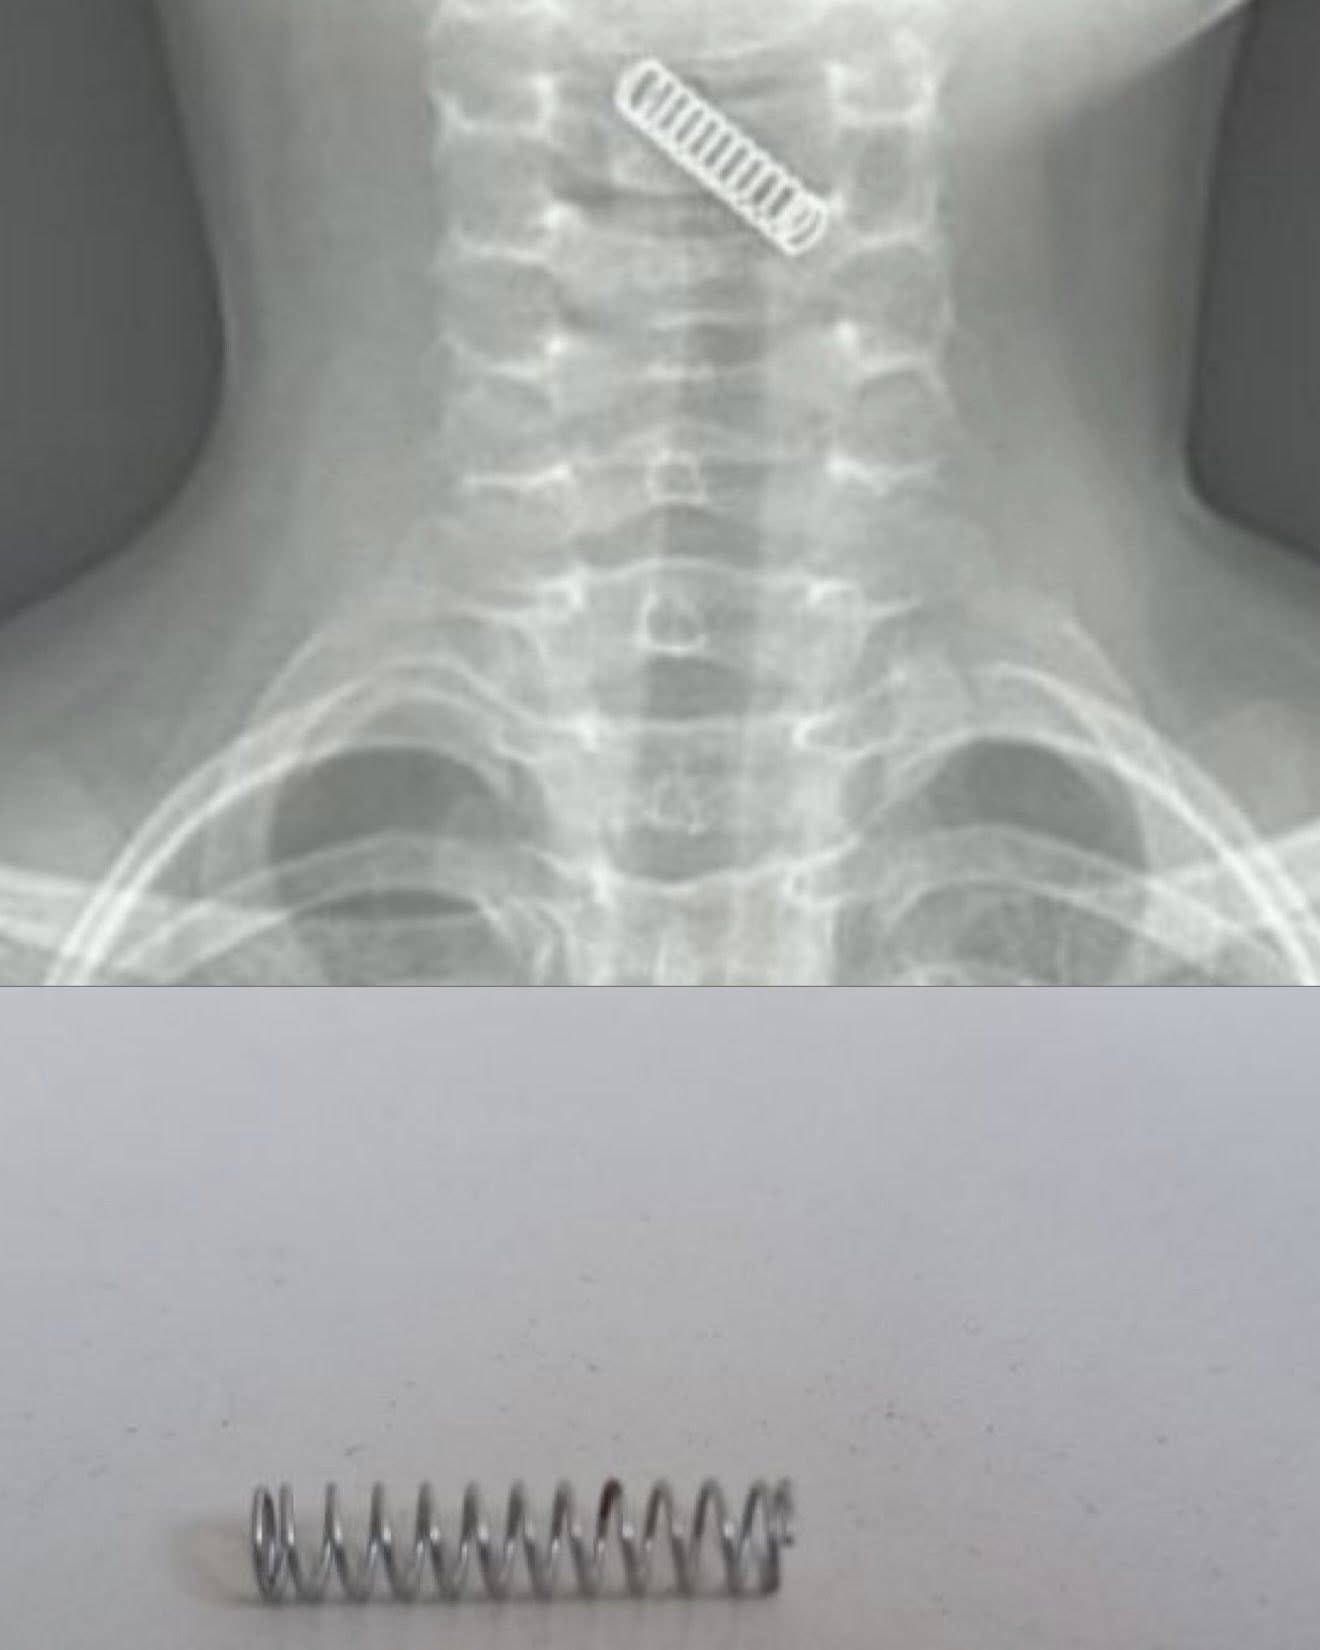

У дописі представлені фото сторонніх тіл, які нашим лікарям доводилось діставати. А також рентген-знімки.

Найчастіше діти ковтають: копійки, батарейки, елементи конструктора LEGO, частини іграшок, стиральну гумку, елемент від викрутки. Буває, що молочні зуби діти вдихають — лікарі їх витягують. В колекції медиків також пульпоекстрактори від стоматологів, канцелярські цвяхи, лампочки з ялинкових прикрас.